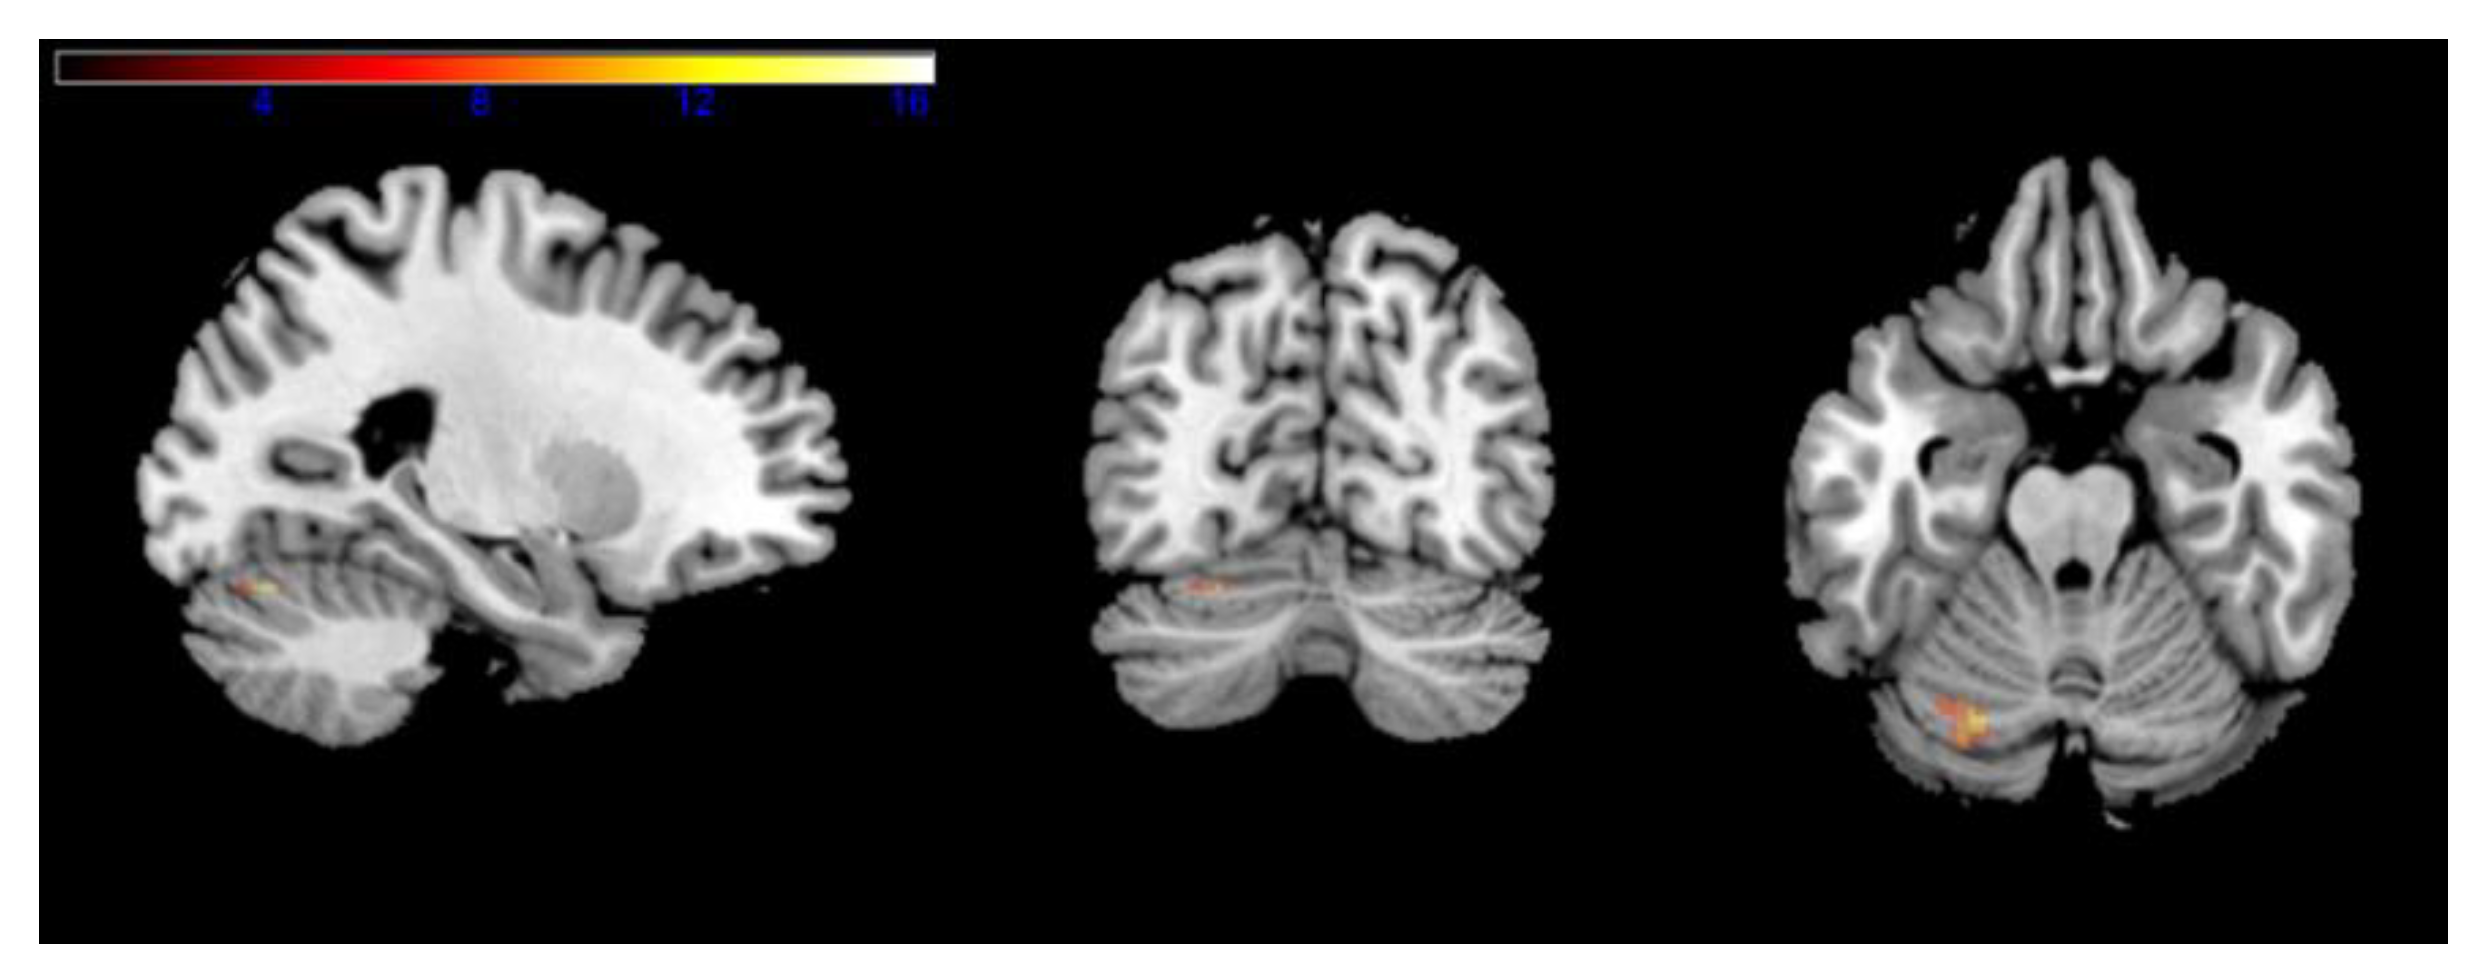

In the whole-brain analysis, no significant differences in activation were found in the low working memory load. Nonetheless, in the high working memory load, the Ai-Chi group presented a decrease in cerebellar activation located in the left cerebellum_6 (based on the AAL atlas) (Figure 2) (Table 3).

Region of interest analyses yielded similar results by which pre-cerebellar activation was higher than post-intervention (M(SD) = 0.42(0.51), M(SD) = 0.19(0.41); t = 2.77, p < 0.05). The on-land Ai-Chi and the guided imagery of Ai-Chi intervention groups did not show any significant differences in activation between the two time points (on land Ai-Chi t = 1.04, p < 0.05; guided imagery of Ai-Chi t = −0.94, p < 0.05).

The second aim of this pilot study was to examine the effects of Ai-Chi intervention for older adults on cerebral activation during a working memory task compared to identical on-land and cognitive non-physical interventions. Our results showed no significant differences in 2-back scores between intervention groups following intervention. In addition, the Ai-Chi group presented a decrease in cerebellar activation located in the left cerebellum_6 in the high working memory load (2-back task). Region of interest analyses yielded similar results by which pre-cerebellar activation was higher than post-intervention. However, the on-land Ai-Chi and the guided imagery of Ai-Chi intervention groups did not show any significant differences in activation between the two time points (pre-intervention and post-intervention). Ai-Chi is characterized as a sequence of continuous movements performed while standing in shoulder-deep water [17]. This provides a multisensory stimulation combining the vestibular, the proprioception and the tactile systems. Immersion increases the proprioceptive input and sensory feedback to the immersed body [31].

Figure 2. Effect of Ai-Chi on the high working memory load brain activation in an n-back task. Maximum intensity projections in three planes of the brain, depicting areas of significant activation (uncorrected, p < 0.001, k > 10) in a one-tailed-t statistic contrasting MR signal. The color scale shows t-values to the right.

Table 3. N-back activation. Table presents regions of activation resulting from a paired t-test threshold to a value of 0.05, k > 10, uncorrected. x, y, z are MNI coordinates for maximum Z score of Peak-level; 2 > 0-back = high working memory load.

Peak MNI Coordinates (mm)Peak-LevelLabel (AAL)

2 > 0-back# voxelsXYZT-scoreZ-score

31−24−70−2216.334.32Cerebellum 6

−32−66−228.123.5Cerebellum 6

−18−76−207.543.41Cerebellum 6